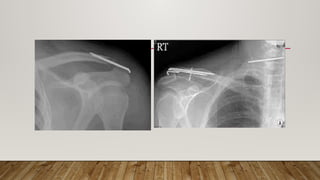

ACROMIOCLAVICULAR

FIXATION

• Hook Plate

• Only used for acute

injury

• Requires subsequent

surgery for removal